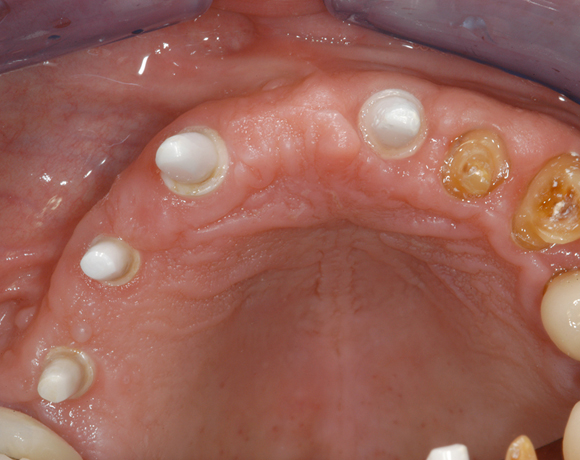

6 Implantate und viele Kronen und Brücken

Mit dem zweiteiligen vollkeramischen Implantat lassen sich auch große Lücken überbrücken.

Im vorliegenden Patientenfall waren die Zähne 11 – 26 mit einer provisorischen Brücke versorgt, der Patient konnte damit aber nicht essen. Auch im Unterkiefer waren die vorhandenen Kronen und Brücken insuffizient. Es wurde eine komplette Neuversorgung für Ober- wie Unterkiefer geplant.